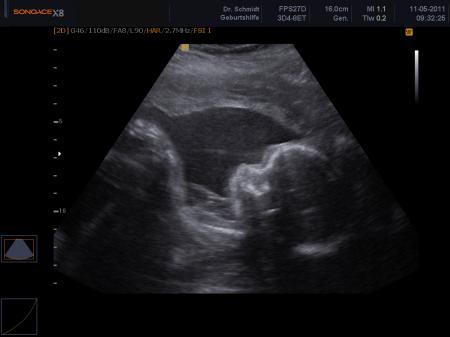

Vom 11.5.11

Bild zu Mal unsere Kleine zeigen muss - Forum für September - Mamis

und hier nochma Ladylike^^ Da die eine Hand so süß töff töff nach unten geht hahahahaha